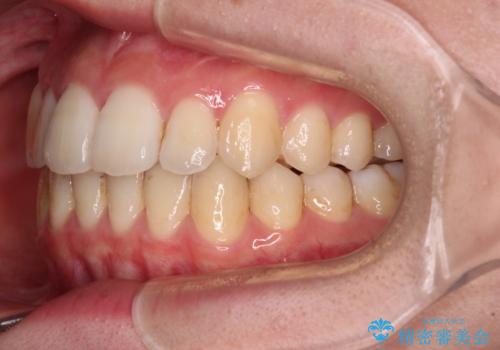

【モニター】前歯の前突感とクロスバイトをインビザラインで改善

- 前歯の突出感とクロスバイトが気になり、インビザラインによる矯正治療を希望して来院された患者様です。

上顎側切歯(上の真ん中から2番目の歯)が舌側転位している場合、インビザラインでは仕上げきれないことが多く、更には無理して動かそうとすると歯髄壊死を起こすリスクが高いと言われています。

インビザラインで歯列を移動する前に、上顎前歯をワイヤー矯正で整え、その後上下歯列をインビザラインにて矯正治療を行うこととしました。

舌側転位している側切歯特有の、切縁の位置が不揃いであったり、根元が内側に引っ込んだ状態であったりという、インビザライン独特の仕上がりになることなく、きれいに整った歯列とすることができました。